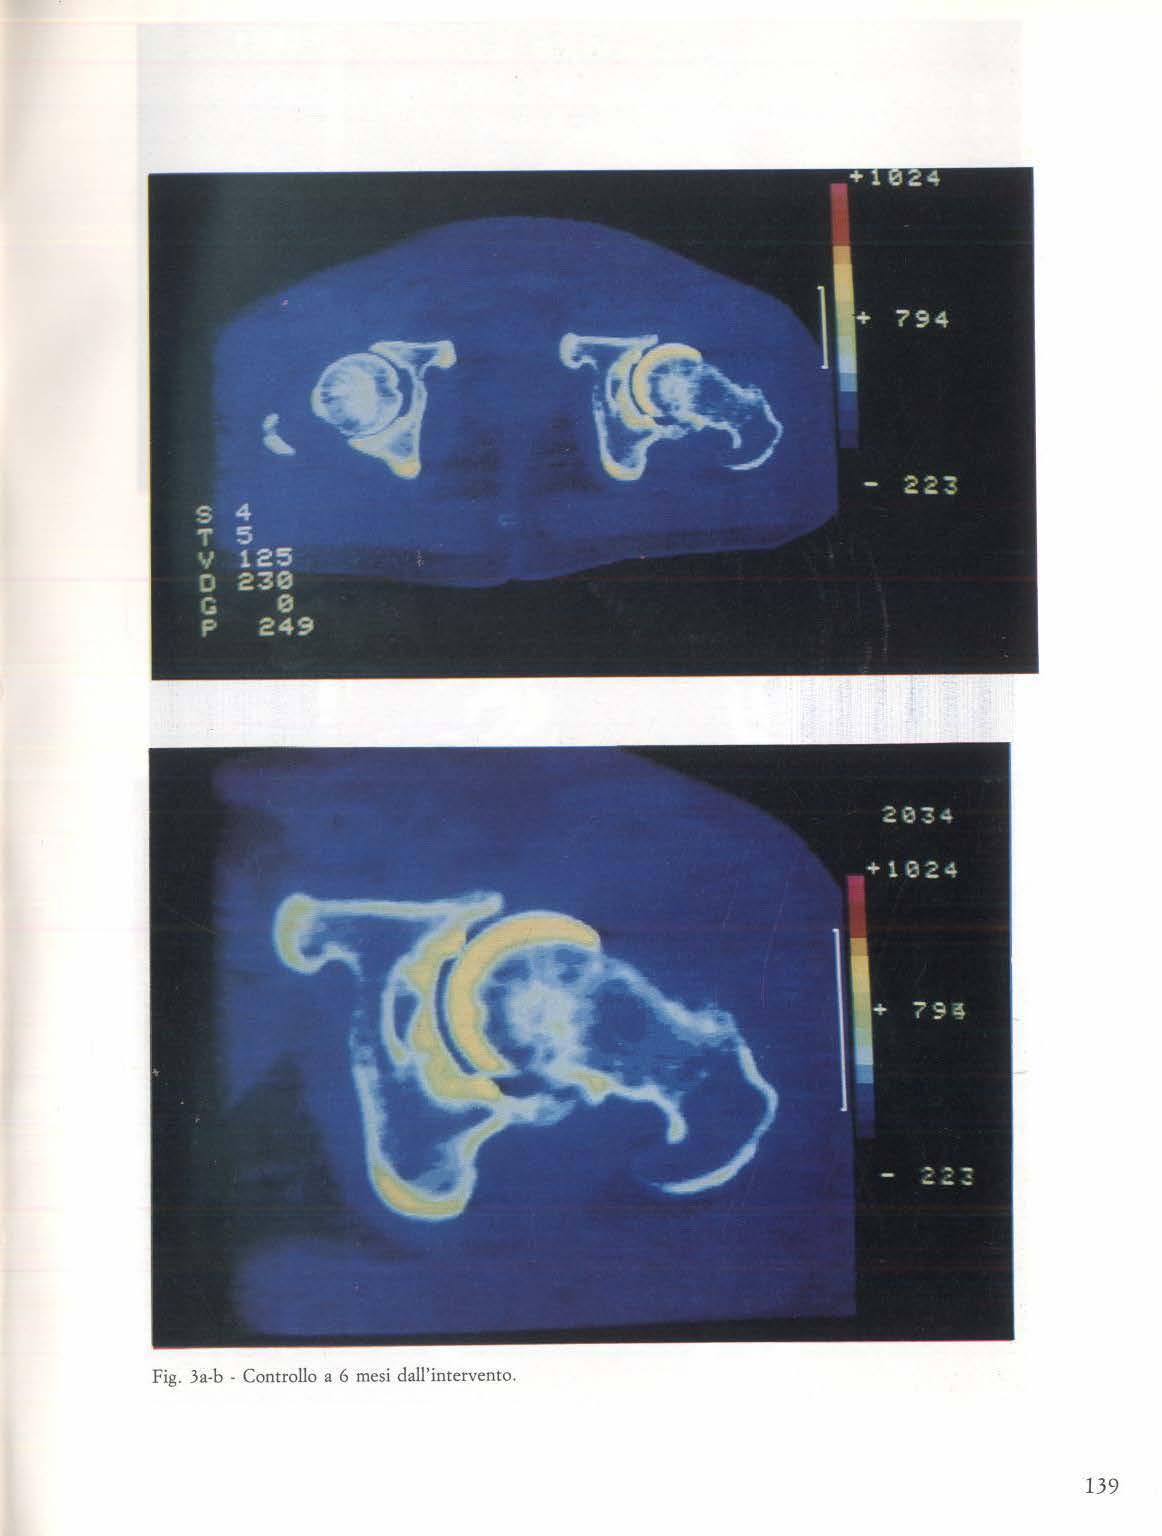

- gruppo 1: reticolazione suddivisa in: tenue, discreta e marcata ( fig. 2a-b; 3a-b ) .

hg. 3a-b: Quadro reticolare di rossicomane dedito ad eroina da 3 anni.

Fig. 2a-b: Aumento dell'opacità di fondo determinante a spetto a «vetro smerigliato » in tossicomane dedito da 3 anni all'uso di eroina.